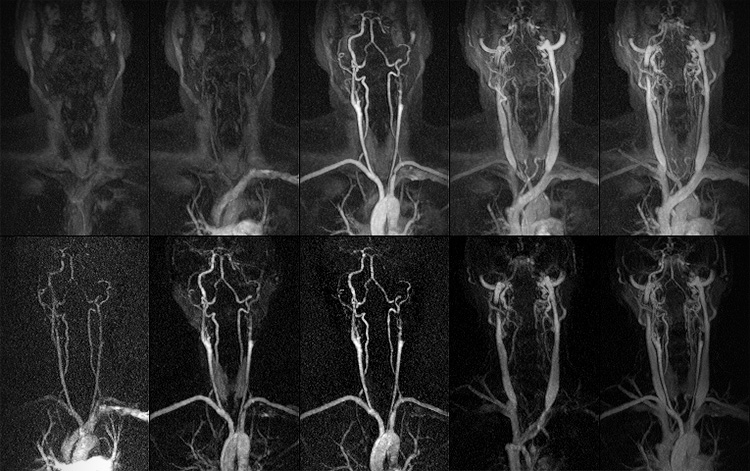

Медицинская диагностика: КТ и МРТ головного мозга